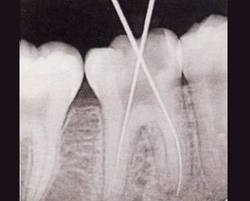

El dentista perfora la pieza afectada y retira la pulpa infectada. Después

limpia, agranda y moldea los conductos de la raíz y, por último, los

rellena con un material que impide la proliferación de gérmenes.